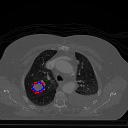

A qualitative analysis of our results reveals the strengths and weaknesses of our proposed model. In most cases, regardless of the size of the ground truth, our model predicts the tumor shapes very well. This is evident from Figure 4 where the ground truth and the prediction (by Deeply Supervised MultiResUNet) are shown in red and blue respectively. Although the tumors are in various arbitrary locations within the lung and appear in diverse sizes, the red and blue margins appear to coincide almost perfectly.